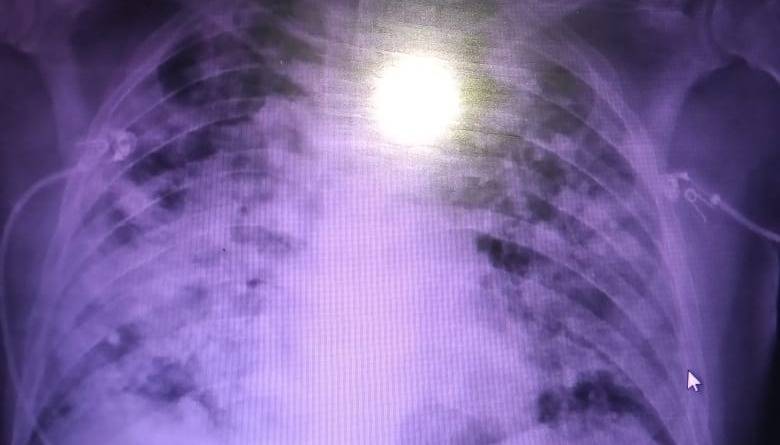

Profundamente conmovida estaba la doctora Silvana Rivero que trabaja en el hospital Papa Francisco y que se enfrenta todos los días con la enfermedad. «Yo les pido que se cuiden, que mantengas las medidas de prevención. Ahora que se viene el Día de la Madre, que las cuiden a sus mamitas, que no salgan, que se mantengan aislados porque ya nadie le importa la pandemia. Nosotros vemos todos los días cómo llegan al hospital y ya no podemos hacer nada. Los familiares se enojan, pero ya no hay solución. Se nos mueren nuestros compañeros en nuestros brazos y la gente no toma conciencia», dijo la doctora Rivero mostrando una foto de un pulmón afectado por coronavirus.